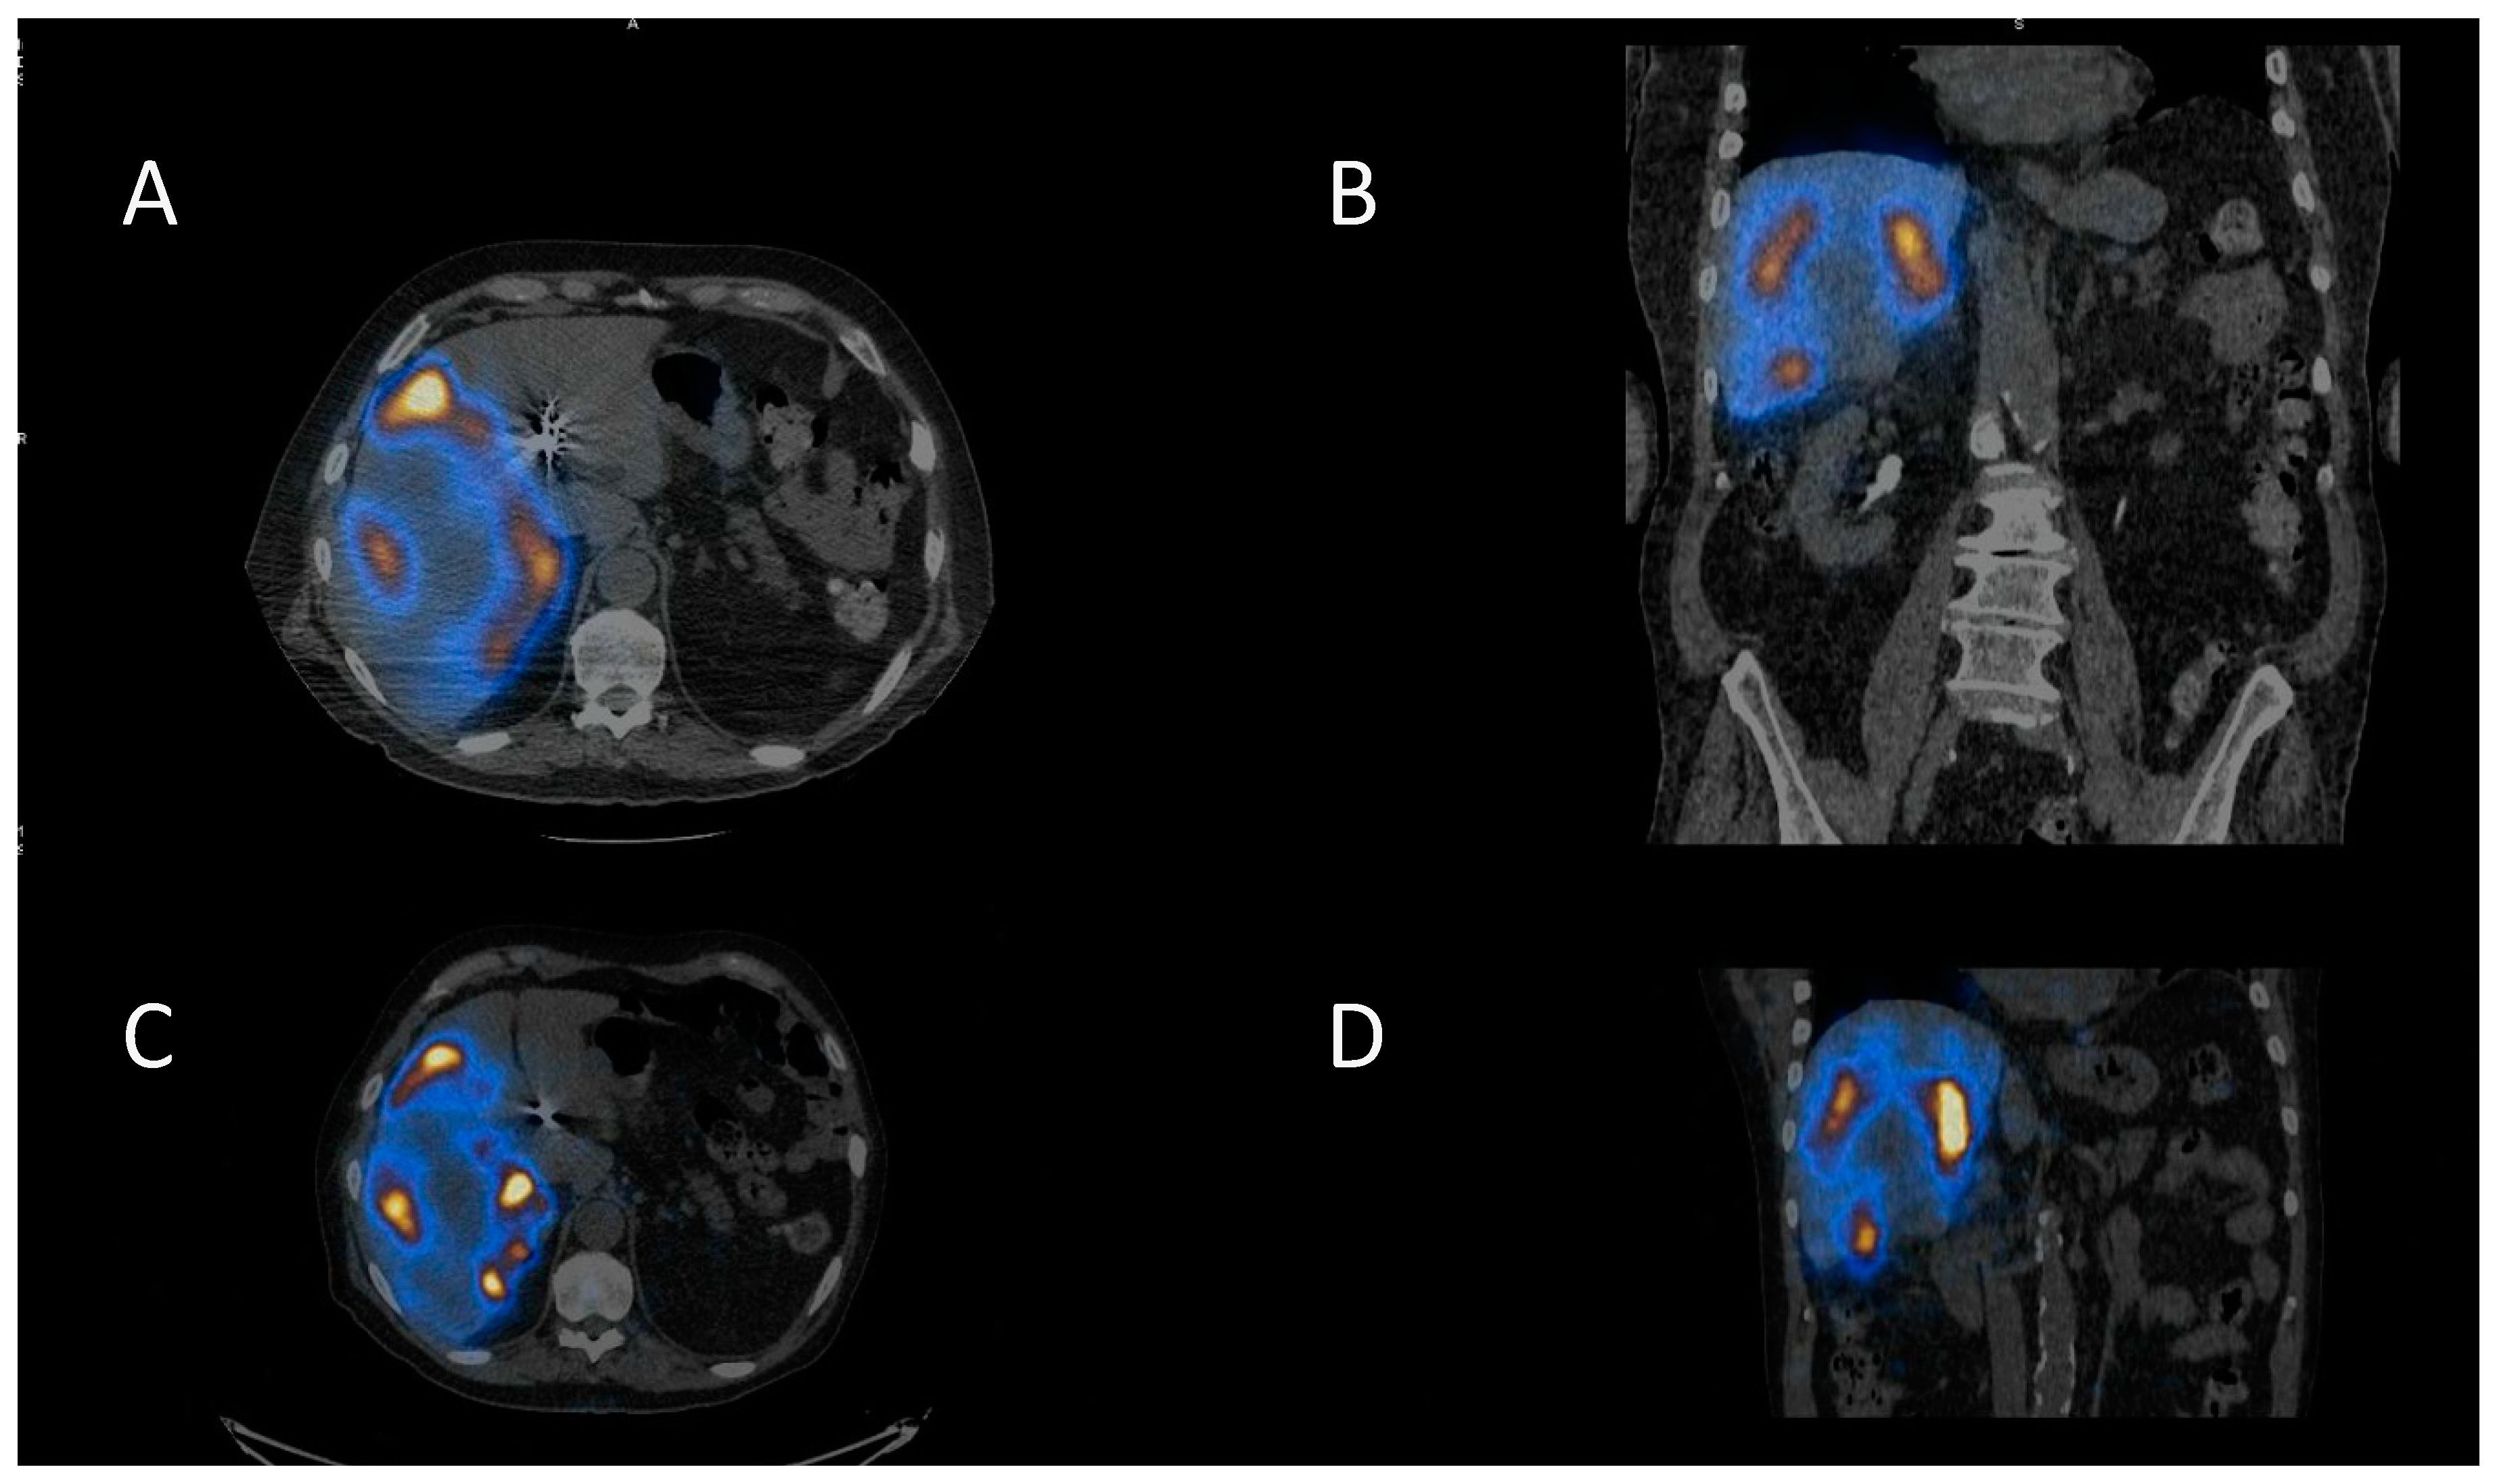

Selective Internal Radiotherapy (SIRT) is a treatment using radiolabelled microspheres to treat liver tumours with indications including hepatocellular carcinoma (HCC) and liver metastases from colorectal cancer (mCRC) [36]. Benefits have been seen for the treatment of liver metastases for some other primary cancers as well [37]. Radiobiologically guided dosing strategies are possible [38]. Patients undergo a hepatic angiogram to perform embolisation to prevent shunting to extrahepatic areas and to administer 99mTc-MAA (macroaggregated albumin) for imaging prior to treatment. The treatment consists of 90Y-microspheres, which are delivered through the same hepatic route to deliver the dose directly to the tumours. The 90Y-microspheres remain in situ, permanently irradiating the tumour sites until the radioactivity physically decays away. The work up imaging allows dose calculation for personalised treatment and allows the identification of shunting. There are two types of 90Y-microspheres: resin spheres at 20–60 µm diameter and glass spheres 20–30 µm. 90Y is a predominantly beta-emitting radioisotope, so imaging can be challenging. Bremsstrahlung imaging or PET imaging is required to image post therapy. A workup with 99mTc-MAA and PET imaging of the 90Y-microspheres is shown in Figure 3.

Figure 3.

Selective internal radiotherapy with radiolabelled microspheres for liver metastases. (A) Axial and (B) coronal fused SPECT CT images of 99mTc-MAA (macroaggregated albumin) pre-treatment imaging for dose calculation and treatment verification. Corresponding (C) axial and (D) coronal post-therapy PET CT images following therapy with 90Y-microspheres.

166Ho–microspheres are a newer product on the market, which are a gamma-emitters and have paramagnetic properties allowing for SPECT and MR imaging. The product also has the option of low-dose 166Ho-microspheres are for the workup to more accurately mimic the treatment, as they use the microspheres themselves for the pre-therapy imaging. [39]